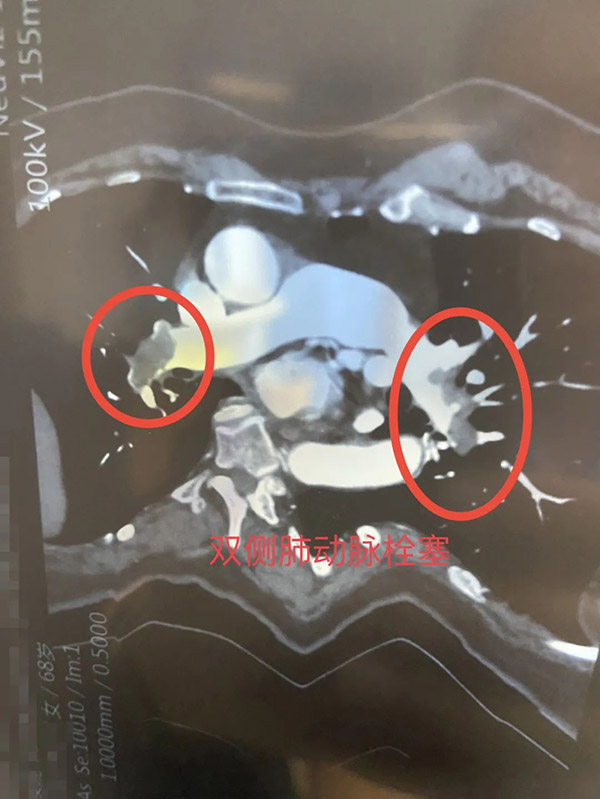

接诊后,心内二科主任陈用贵为齐女士详细检查,发现其有肺高压的情况,下肢静脉彩超提示双下肢深静脉血栓形成,肺动脉CTA显示双侧肺栓塞。诊断为急性肺栓塞下肢深静脉血栓,情况较为危急。